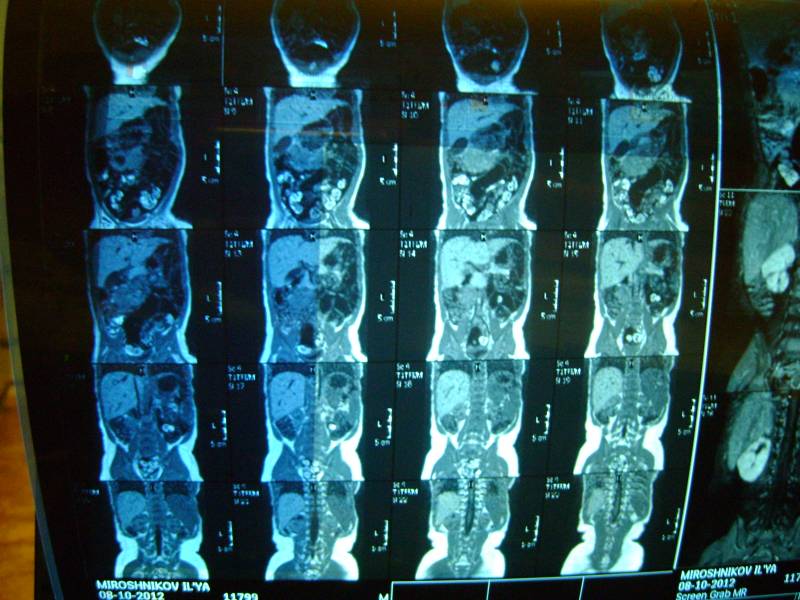

Уважаемый доктор просим посмотреть снимки и нашего сына! Возраст 10 мес. два близнеца однояйцевых у одного поликистоз у второго нет. Можно ли понять тип поликистоза детский или взрослый? Можно ли отправить диск со снимками мрт Вам если можно то куда? К генетикам пойдем в ближайшую среду. Заранее огромное спасибо!!! Попробуем еще фото выложить

Добавляем еще фото